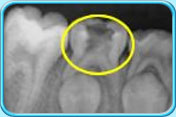

图中所见是一张X光片,显示一颗牙髓还没坏死的乳臼齿。治疗前

图中所见是一张X光片,显示一颗接受了清除部分牙髓的治疗之后的乳臼齿。治疗后